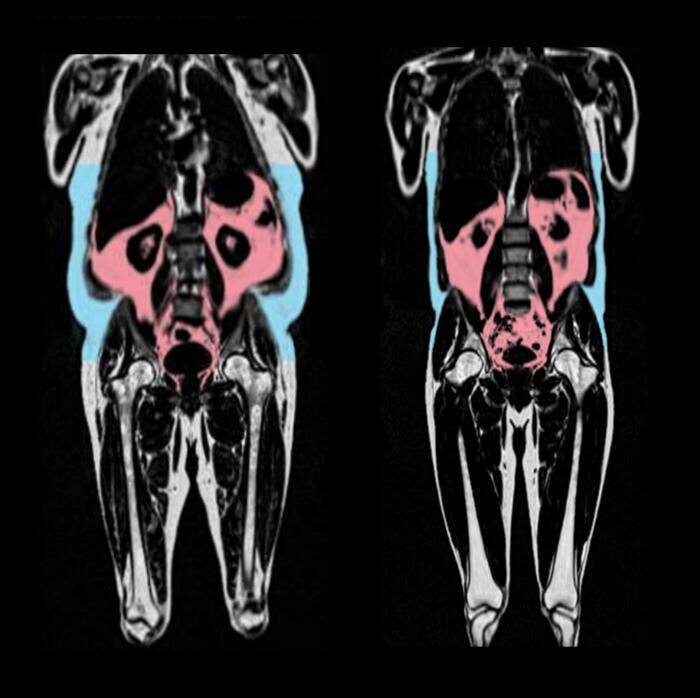

Даже при нормальном весе избыток жира вокруг внутренних органов — так называемый висцеральный жир — может быть крайне опасен для сердца. Он не виден на глаз, но оказывает серьезное влияние на работу сердечно-сосудистой системы:

Согласно научным данным, особенно у мужчин с накоплением жира в области живота, висцеральный жир напрямую влияет на биологические процессы сердца, ускоряя его старение и повышая риск сердечно-сосудистых заболеваний.

⚠️ Важно: висцеральный жир опасен даже при нормальном внешнем весе. Он действует тихо, но разрушительно, ускоряя старение сердца и повышая риск инфаркта, инсульта и сердечной недостаточности.